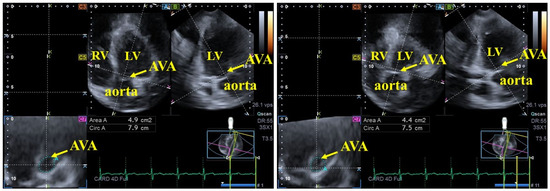

Introduction. The etiology of cardiac amyloidosis (CA) involves the systemic or localized deposition of misfolded amyloid proteins within the myocardial interstitium and valvular structures. The primary objective of this study was to employ three-dimensional speckle-tracking echocardiography (3DSTE) to perform a detailed analysis of [...] Read more.

Introduction. The etiology of cardiac amyloidosis (CA) involves the systemic or localized deposition of misfolded amyloid proteins within the myocardial interstitium and valvular structures. The primary objective of this study was to employ three-dimensional speckle-tracking echocardiography (3DSTE) to perform a detailed analysis of the aortic valve annulus (AVA) and left ventricular (LV) strains in CA patients and to compare these parameters with those of matched healthy controls. Methods. The initial cohort for this study comprised 35 individuals diagnosed with CA. However, 12 patients were subsequently excluded from the final analysis due to suboptimal image quality precluding accurate measurement of AVA dimensions and/or LV strains. The final analytical group, therefore, consisted of 23 CA patients (14 males), with a mean age of 64.6 ± 7.1 years. The results obtained from the CA patient group were compared with those of a healthy control cohort comprising 23 individuals (14 males; mean age: 53.2 ± 5.3 years). Results. In CA patients, AVA area was greater in end-diastole in 11 out of 23 cases (48%), and in end-systole in 8 out of 23 cases (35%), while it proved to be equal in 4 out of 23 cases (17%). The ratio of healthy controls with greater end-diastolic AVA area (12 out of 23, 52%) and greater end-systolic AVA area (11 out of 23, 48%) did not differ from that of CA patients. End-diastolic and end-systolic maximum and minimum AVA diameters, areas and perimeters did not differ between CA patients and matched controls. AVA plane systolic excursion (AAPSE) was found to be significantly impaired in all CA patients irrespective of AVA area size. Basal LV radial (RS), circumferential (CS) and longitudinal (LS) strains were reduced in CA patients compared with those of controls. End-systolic AVA dimensions tended to be reduced in CA patients with greater end-diastolic AVA area compared with those with greater end-systolic AVA area. While basal LV-RS and LV-CS proved to be similar between CA subgroups, basal LV-LS tended to be higher in CA patients with greater end-systolic AVA area. Controls with greater end-diastolic AVA area showed lower basal LV-RS and LV-LS compared with those with greater end-systolic AVA area. CA patients with equal end-diastolic and end-systolic AVA area (n = 4) showed similarly reduced AAPSE, basal LV-RS, basal LV-CS and LV-LS. Conclusions. In the presence of CA, the AVA is not dilated; however, its spatial displacement is reduced, suggesting its functional impairment, as represented by AAPSE, possibly due to the reduction in all concomitant LV strain parameters. Full article